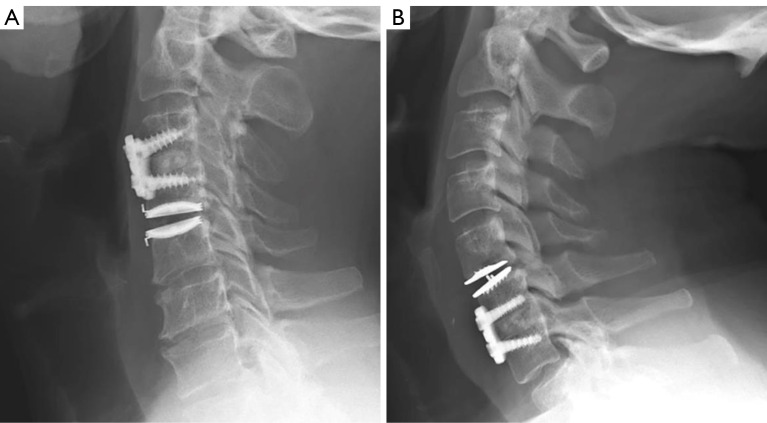

Background: Traditional surgical treatment for symptomatic cervical degenerative disc disease is anterior cervical discectomy and fusion (ACDF), yet the increased risk of adjacent segment degeneration (ASD) requiring additional surgery exists and may result in limiting long-term surgical success when it occurs. Disc arthroplasty can preserve or restore physiologic range of motion (ROM), decreasing adjacent level stress and subsequent surgery. For patients with multilevel pathology requiring at least a 1-level fusion, interest is growing in anterior cervical hybrid (ACH) surgery as a partial motion-preserving procedure to decrease the adjacent level burden. This radiographic study compares postoperative superior adjacent segment motion between ACH and ACDF. Secondarily, total global motion, construct motion, inferior adjacent segment motion, and sagittal alignment parameters were compared.

Methods: This is a single-center, multi-surgeon, retrospective cohort study of 2- and 3-level ACH and ACDF cases between 2013 and 2021. Degrees of motion were analyzed on flexion/extension views using Cobb angles to measure global (C2-C7) construct and adjacent segment lordosis. Neutral lateral X-rays were analyzed for alignment parameters, including global lordosis, cervical sagittal vertical axis (cSVA), and T1 slope (T1S). Differences were determined by independent t-test and Fisher's exact test.